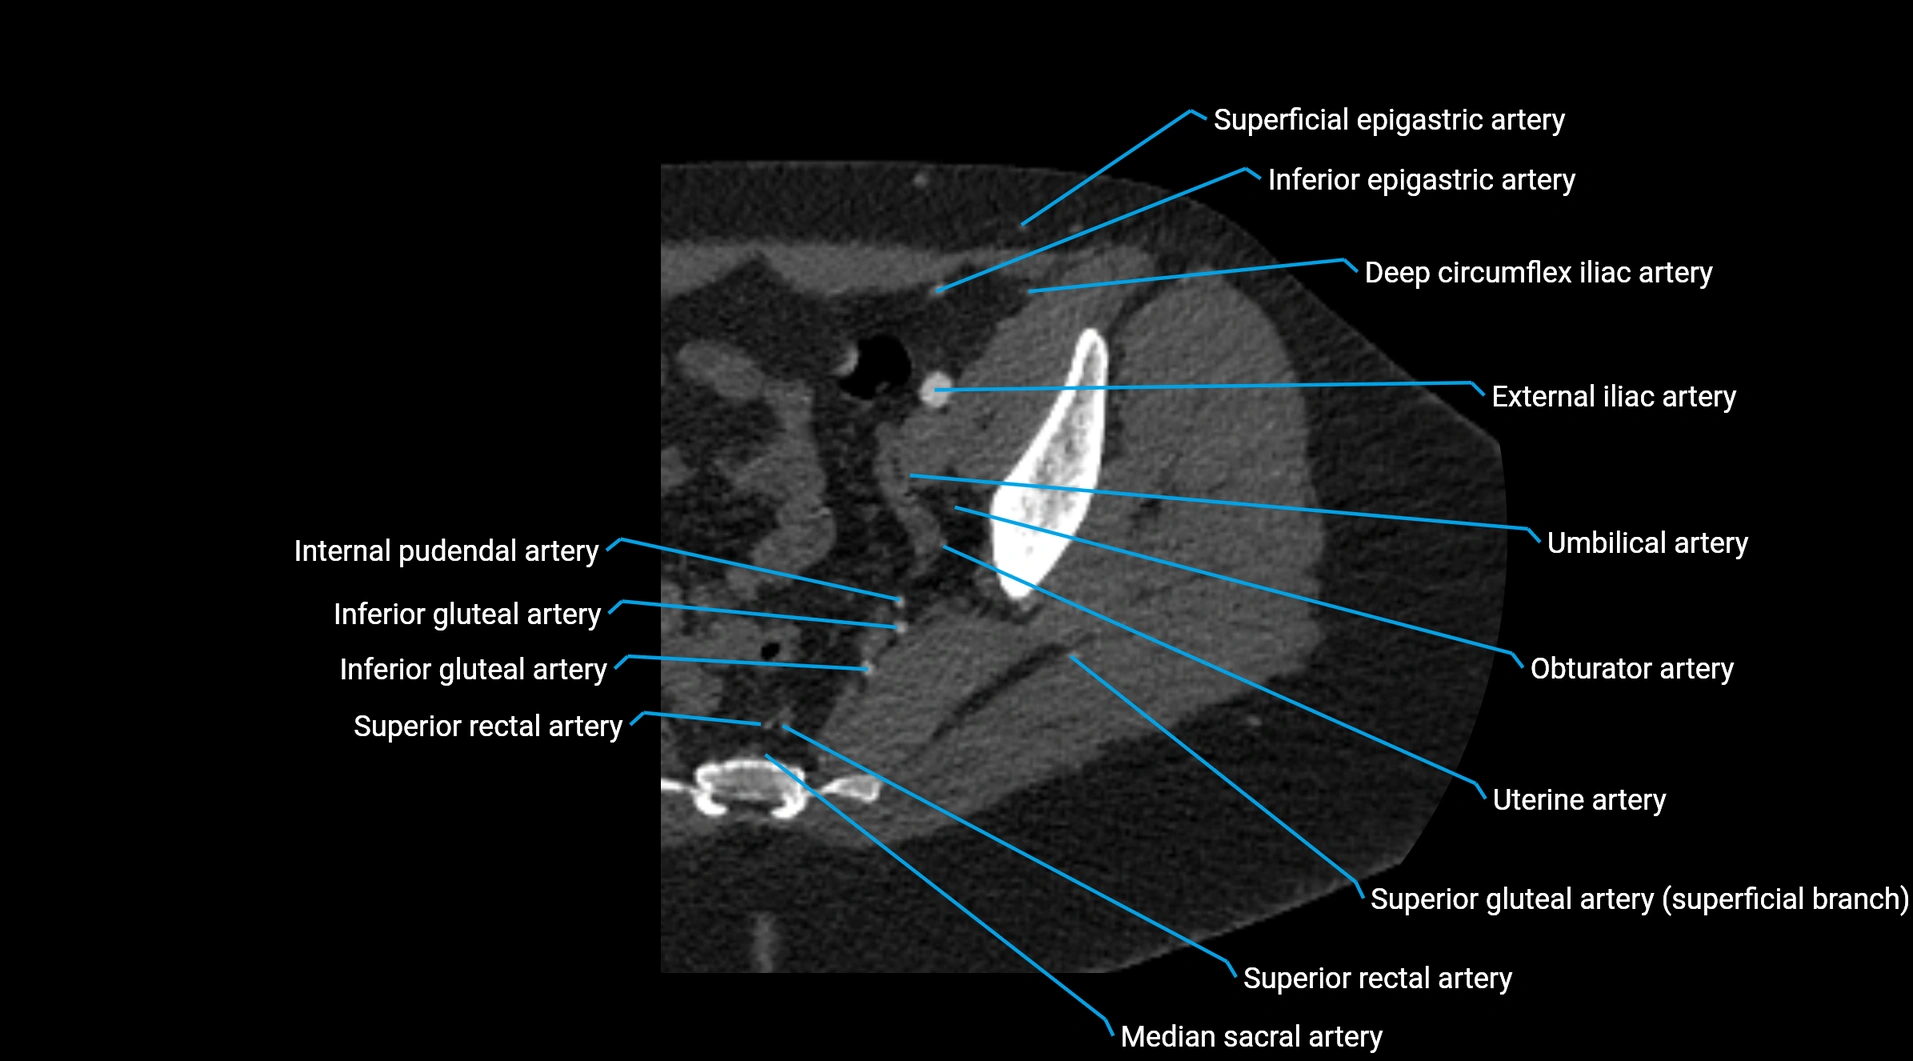

CT Appearance

Non-contrast CT:

• Appears as a tubular soft tissue structure anterior to vertebral bodies

• Calcified atherosclerotic plaques appear as hyperdense foci along the wall

• Useful for screening abdominal aortic aneurysm (AAA) size and mural calcification

Contrast-enhanced CT (CTA):

• Gold standard for abdominal aortic imaging

• Provides excellent detail of lumen, wall, aneurysm, thrombus, and branch vessels

• Multiplanar and 3D reconstructions help in aneurysm measurement, stent graft planning, and dissection evaluation

• Detects acute rupture, traumatic injury, or occlusion with high sensitivity